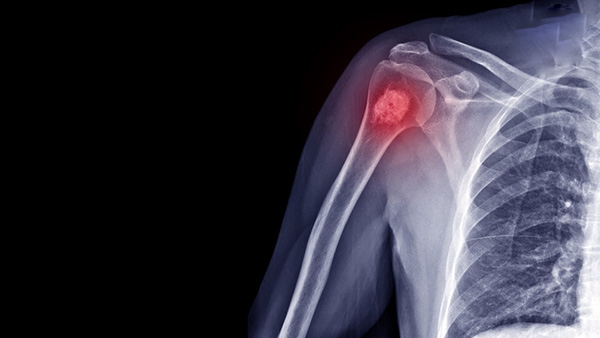

Ung thư xương là căn bệnh ác tính hiếm gặp, chỉ chiếm khoảng 1% trong các...